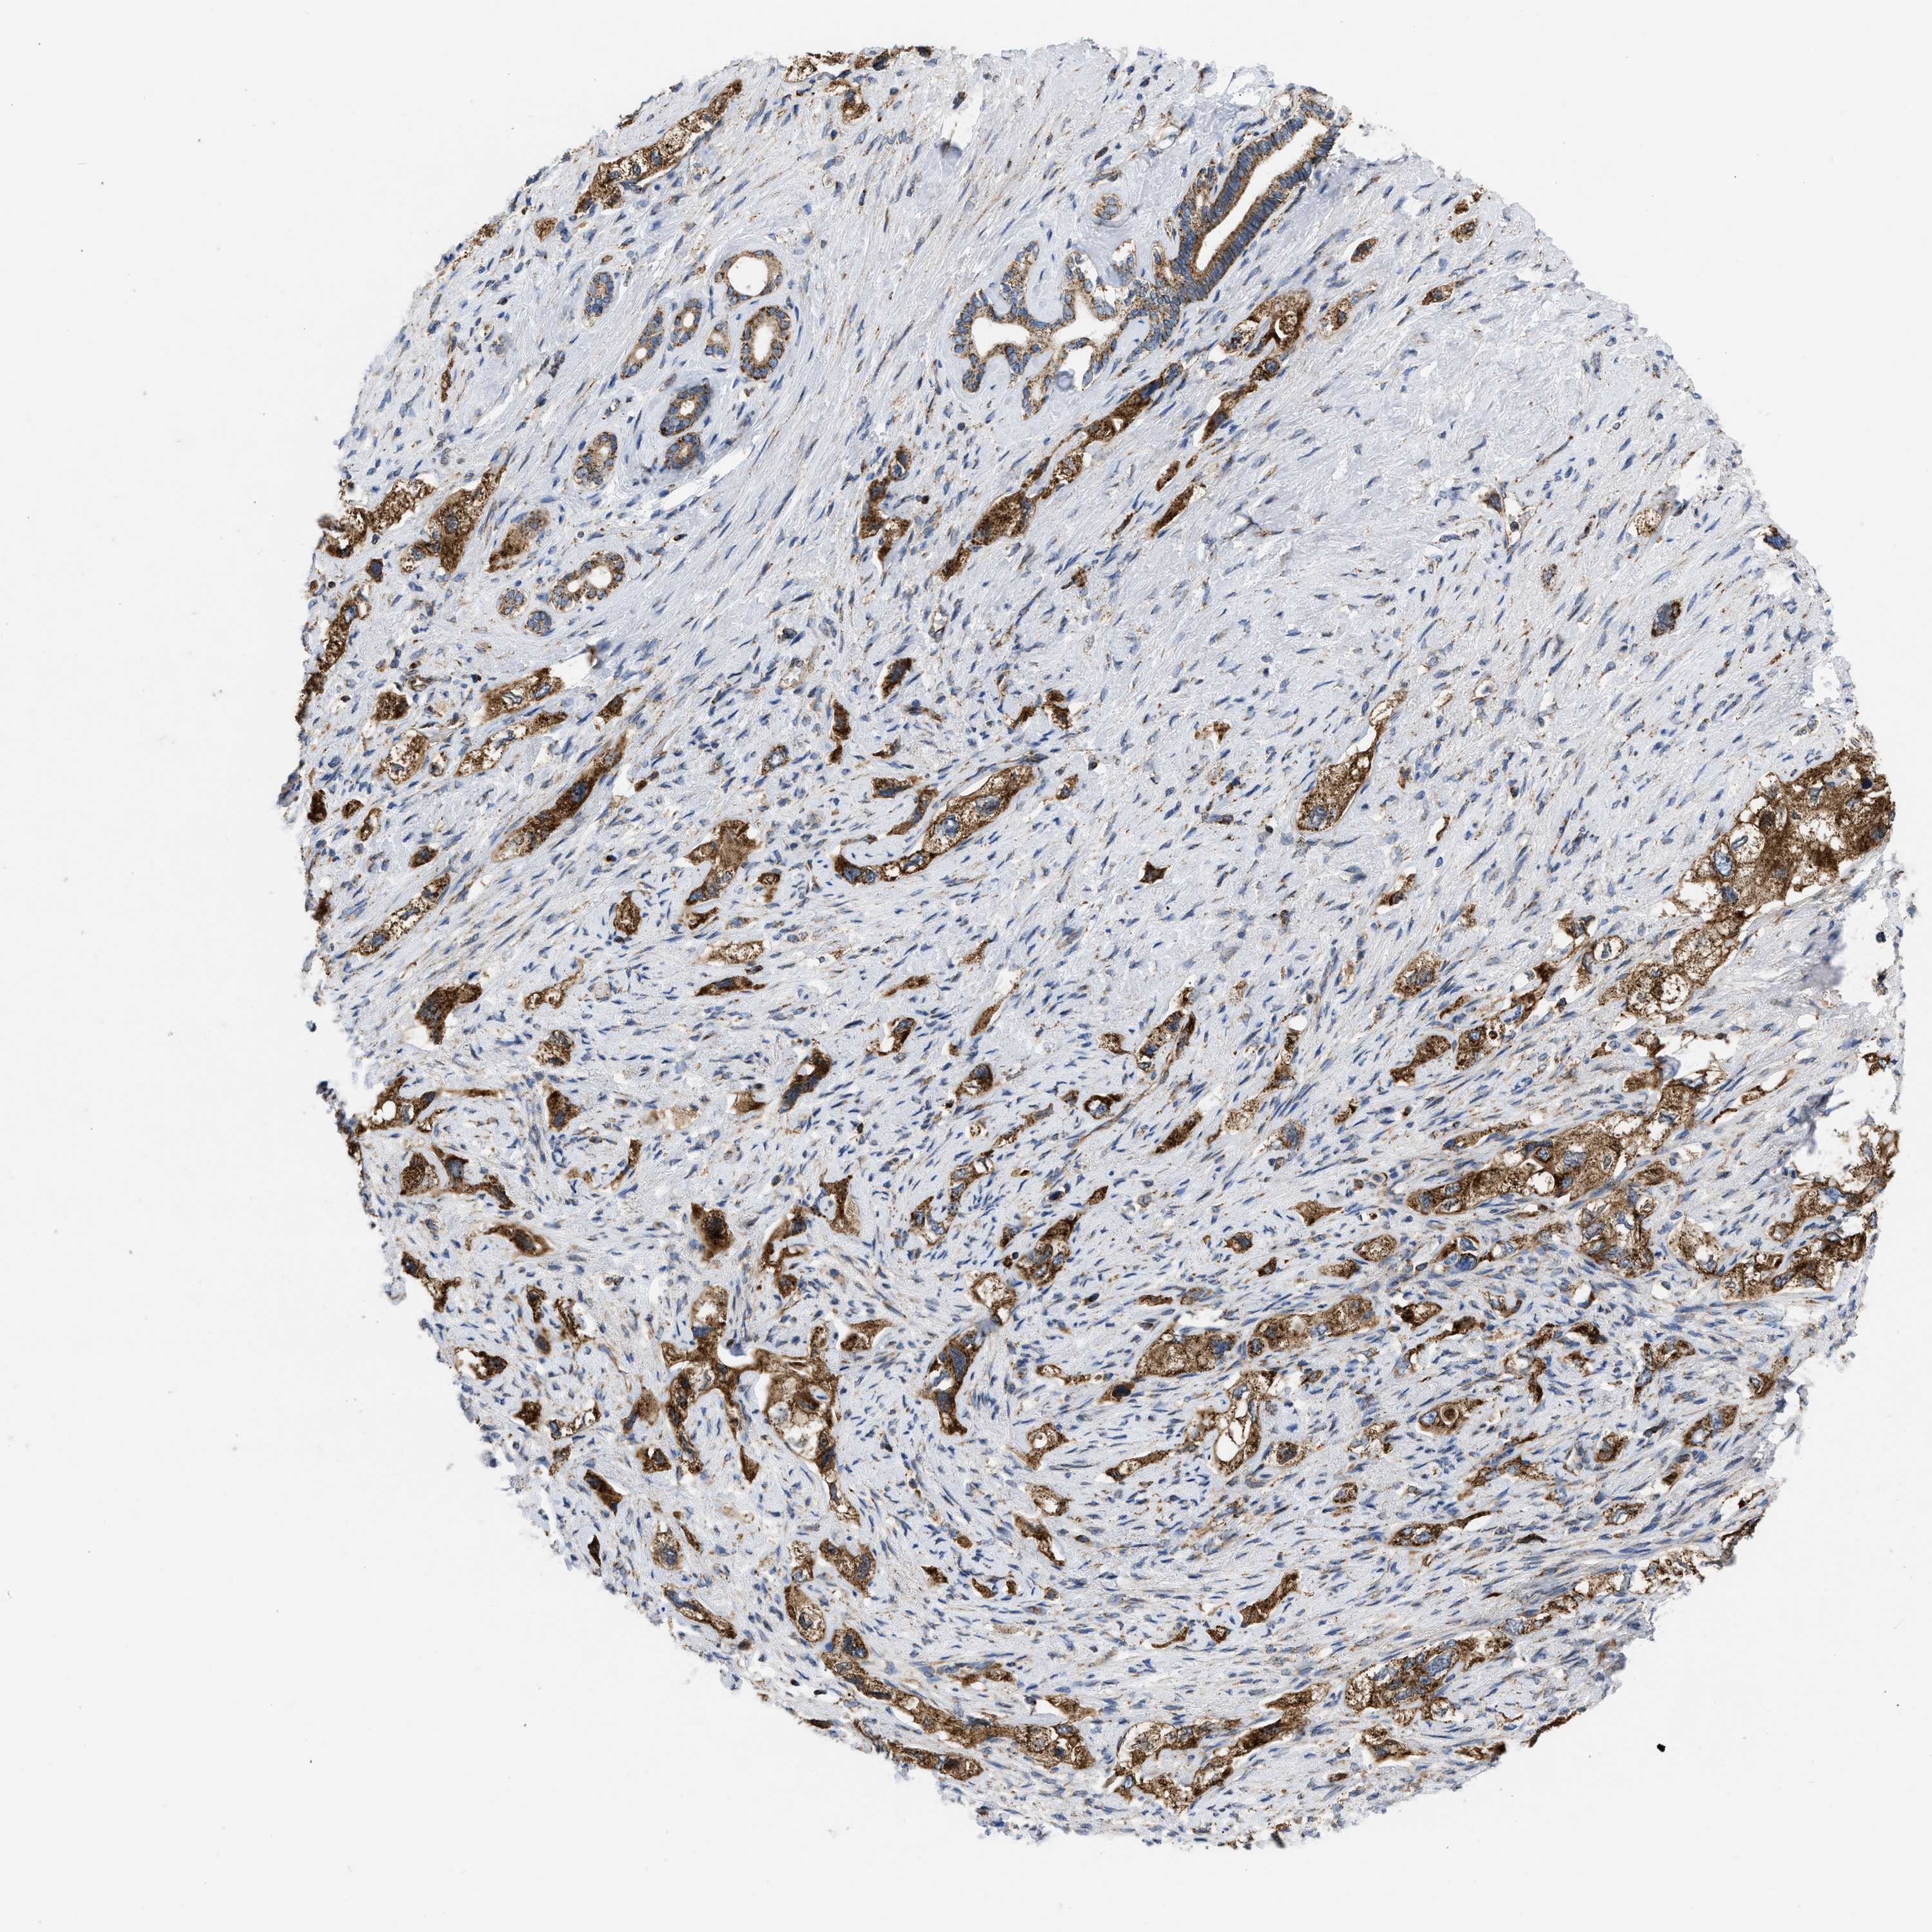

PANCREATIC CANCER - Protein expressioni

A mouse-over function shows sample information and annotation data. Click on an image to view it in a full screen mode. Samples can be filtered based on level of antibody staining by selecting one or several of the following categories: high, medium, low and not detected. The assay and annotation is described here.

Note that samples used for immunohistochemistry by the Human Protein Atlas do not correspond to samples in the TCGA dataset.

Antibody stainingi

Antibody staining in the annotated cell types in the current human tissue is reported as not detected, low, medium, or high, based on conventional immunohistochemistry profiling in selected tissues. This score is based on the combination of the staining intensity and fraction of stained cells.

Each image is clickable and will lead to virtual microscopy that enables deeper exploration of all samples and also displays staining intensity scores, fraction scores and subcellular localization as well as patient and tissue information for each sample.

Antibody HPA003279

Antibody HPA003360

Antibody CAB019303

Staining

High

Medium

Low

Not detected

Intensity

Strong

Moderate

Weak

Negative

Quantity

>75%

75%-25%

<25%

None

Location

Nuclear

Cytoplasmic/membranous

Cytoplasmic/membranous,nuclear

Adenocarcinoma, NOS

Adenocarcinoma, metastatic, NOS